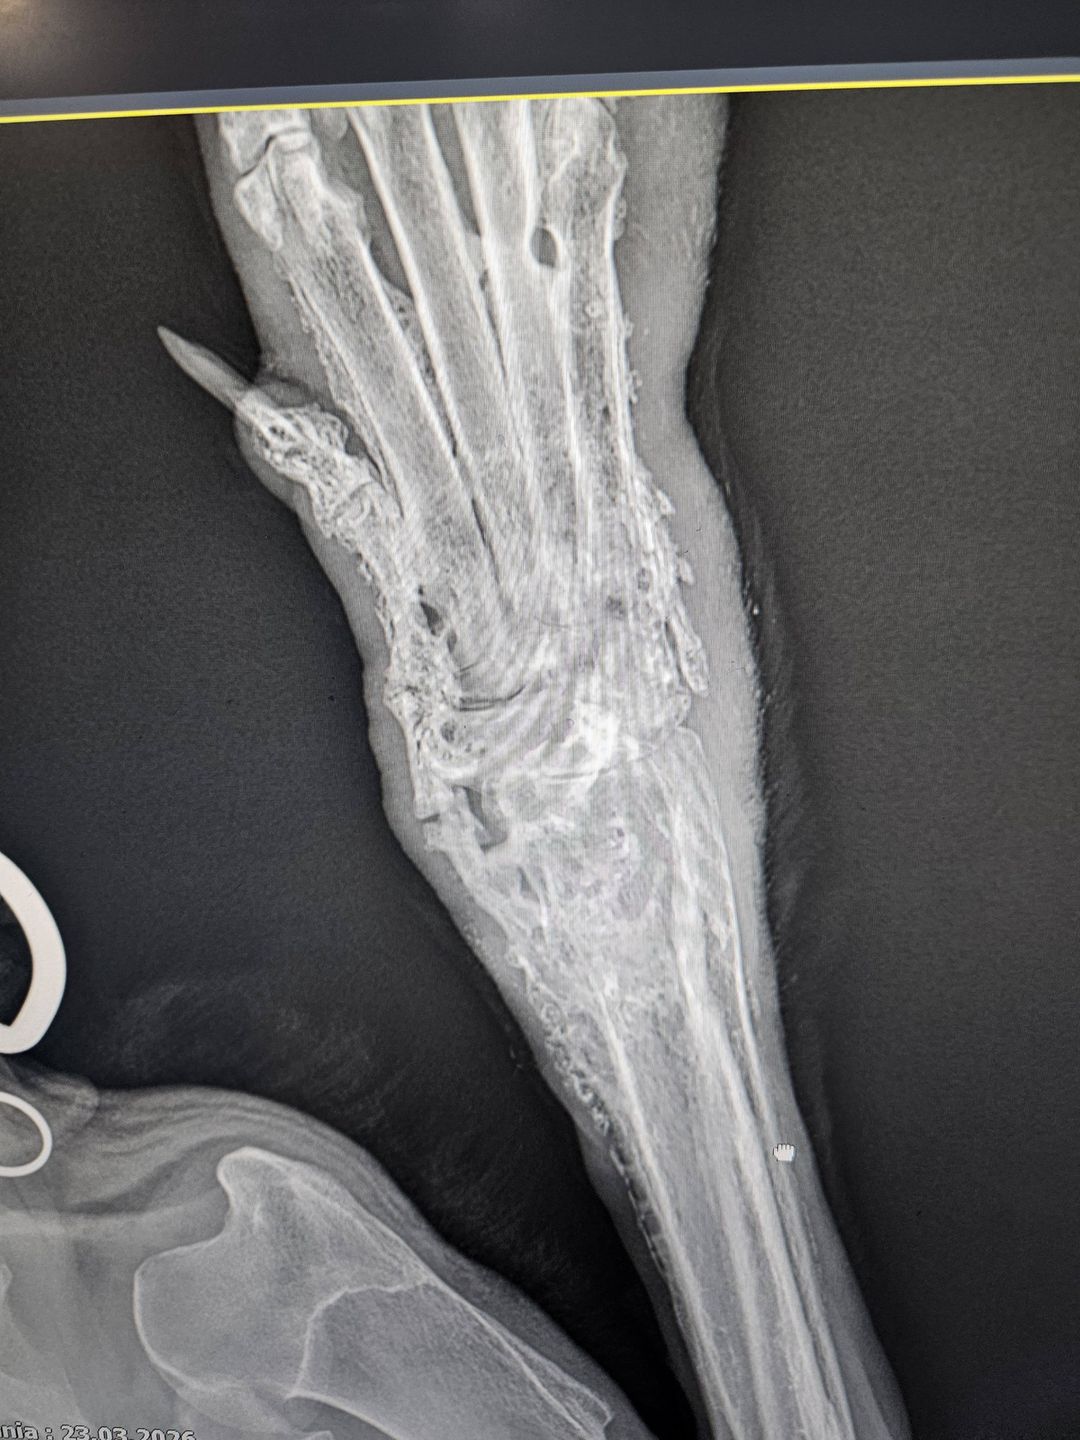

Weterynarze nie mają wątpliwości – stan psa jest bardzo ciężki i wymaga natychmiastowej pomocy. U Lucky’ego zdiagnozowano:

• nowotwór kości – konieczna pilna amputacja łapy